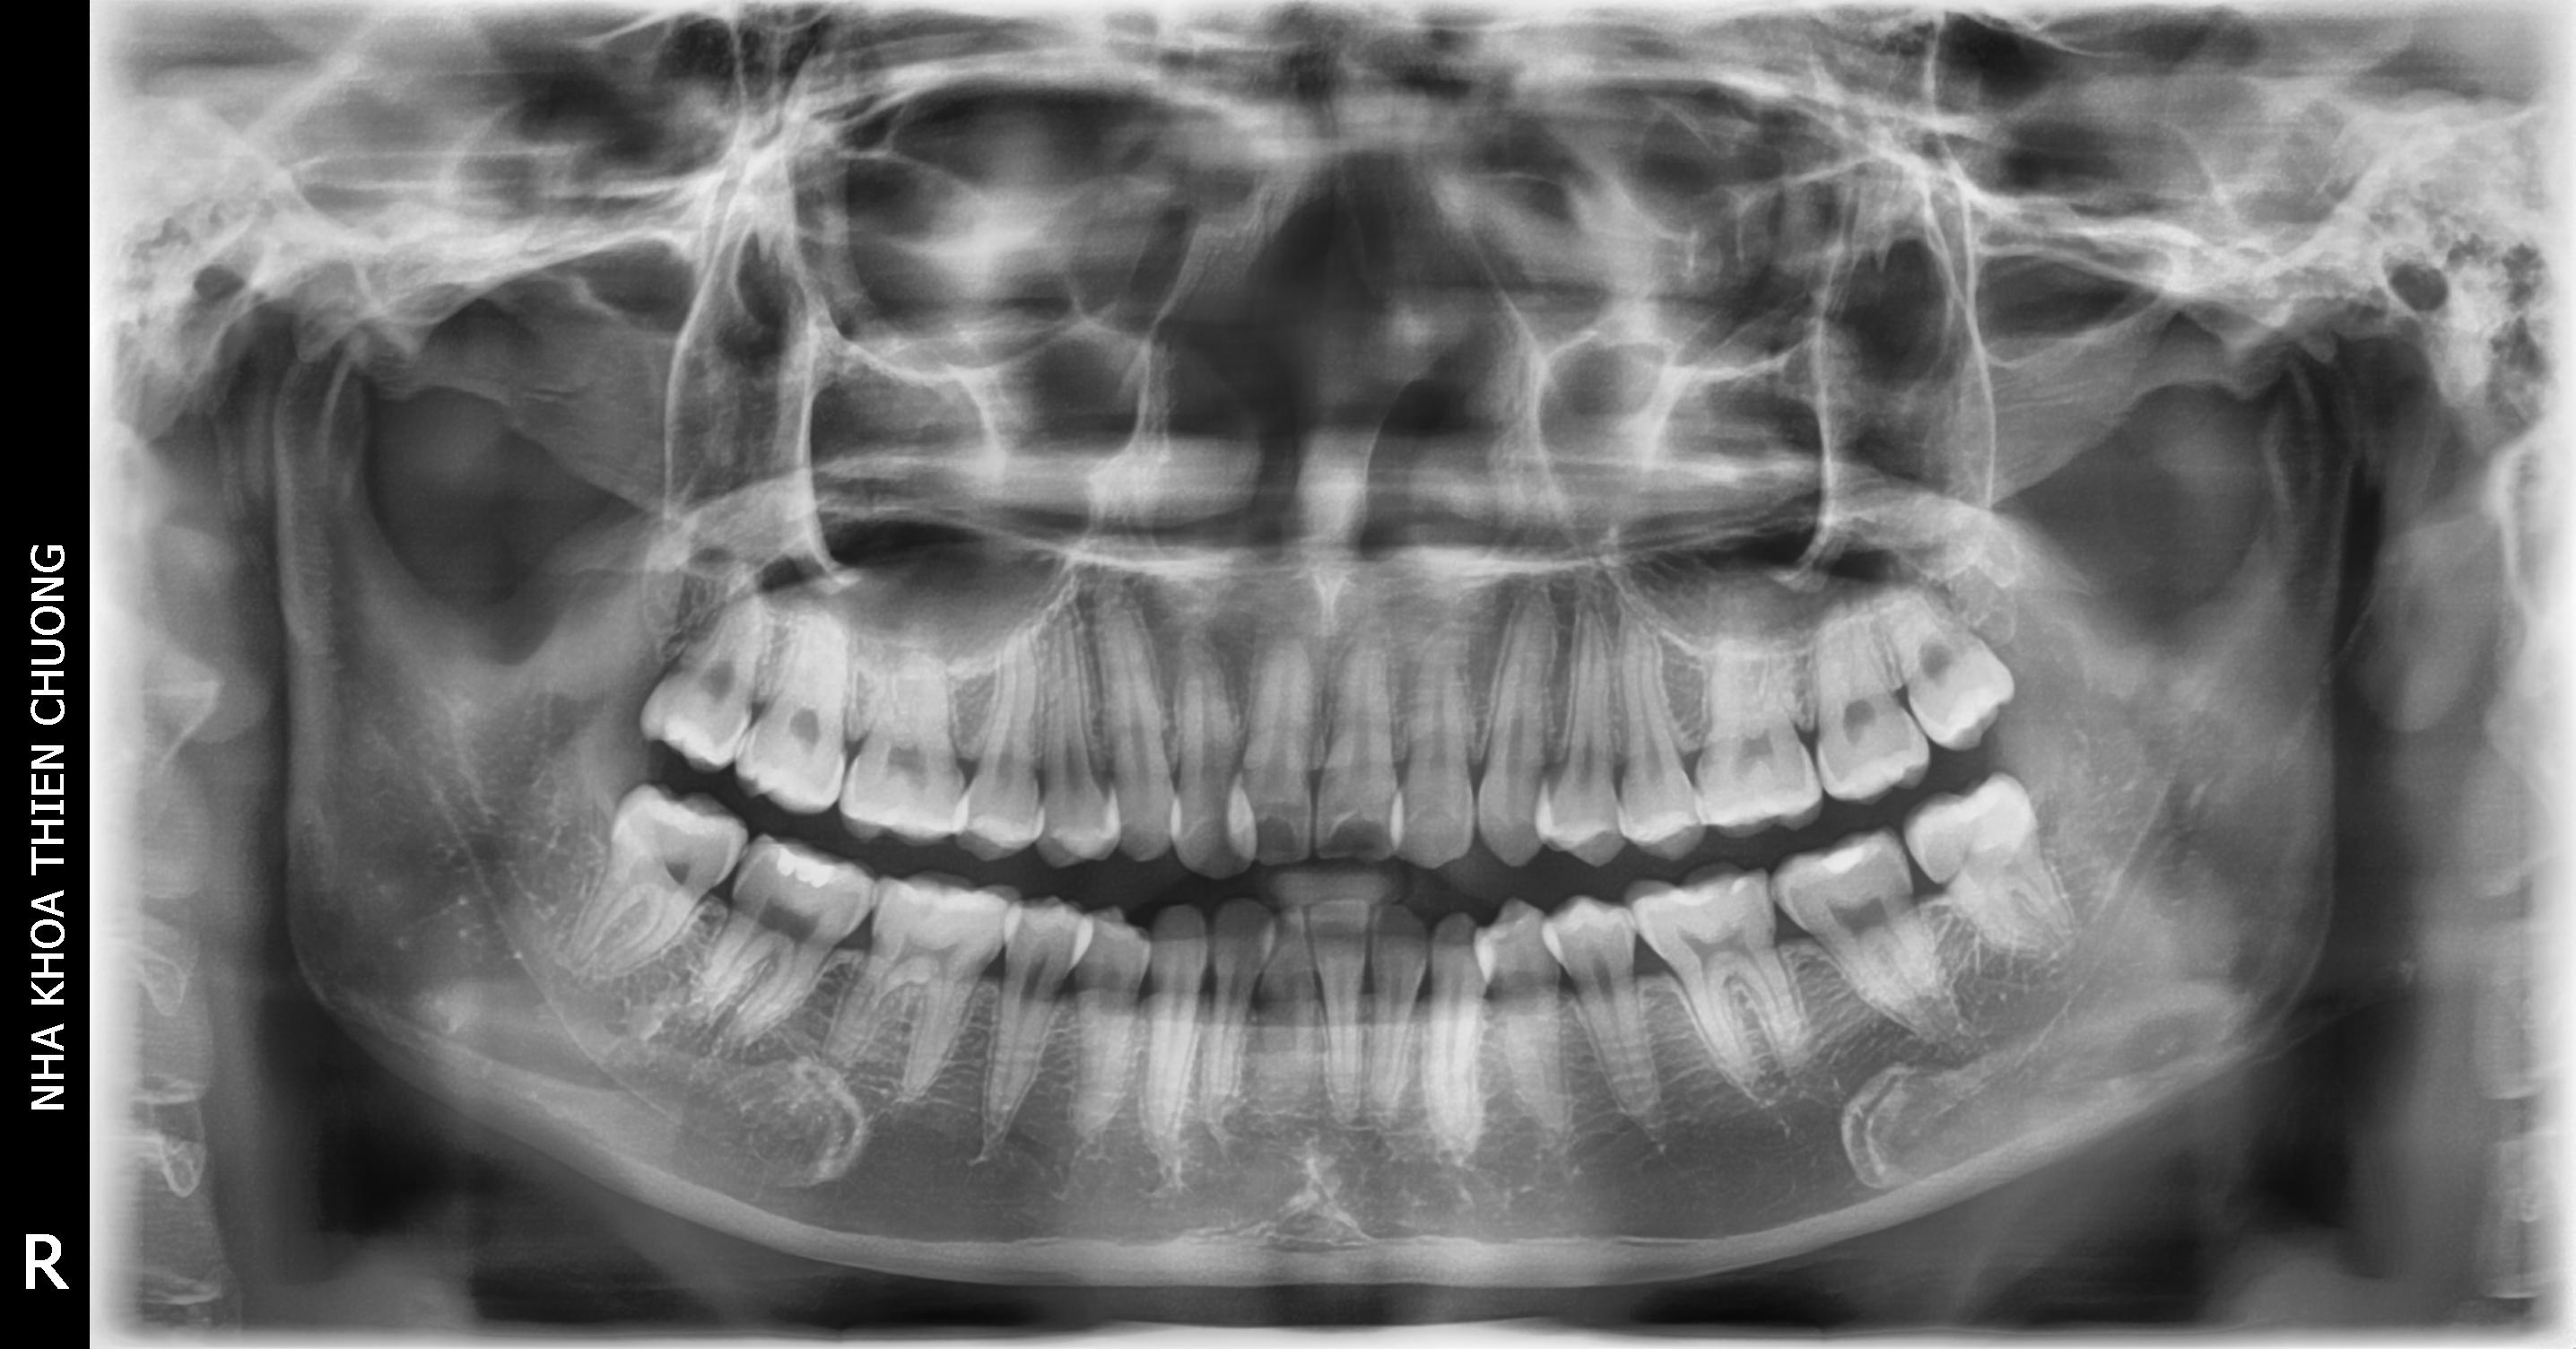

- Khi khám tổng thể sức khỏe răng, nha chu (toàn bộ khu vực xung quanh răng) và các cấu trúc trong miệng; ngoài kiểm tra trực tiếp của nha sĩ về tình trạng răng, nha chu thì việc chụp phim là cần thiết để đánh giá đầy đủ và chính xác tình trạng xương hàm và các cấu trúc bên trong.

+ Phim X – quang toàn cảnh: cung cấp hình ảnh cho thấy được                          toàn bộ tình trạng xương hàm, răng, nha chu; xác định được vị                           trí răng sâu, răng ngầm, răng đã lấy tủy, răng bị nhiễm trùng.